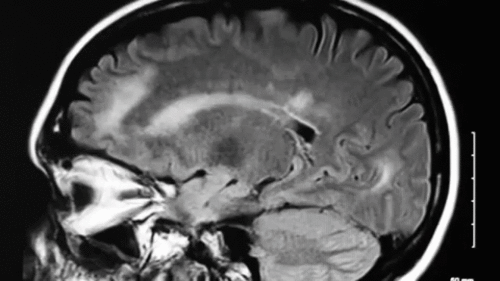

M.B (Theo CNBC)